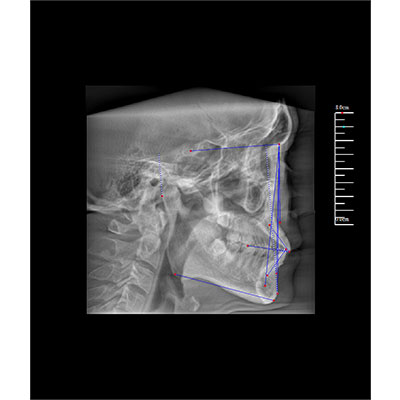

該款牙科CBCT產(chǎn)品采用動(dòng)態(tài)平板探測器,獲得三維圖像的同時(shí)還具有數(shù)字化全景功能,廣泛應(yīng)用于口腔頜面外科、正畸科、正頜外科、種植科、牙體科、顳下頜關(guān)節(jié)科等術(shù)前術(shù)后。

專有三維重建算法,可提供任意位置高清斷層影像。

可同時(shí)觀察軸向面、冠狀面和矢狀面圖像,方便臨床診斷。